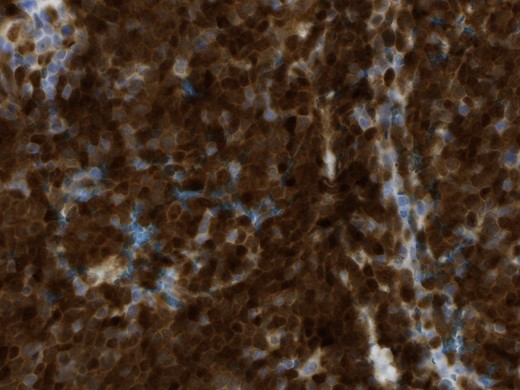

In the pathological assessment the appendix measured 10 and 4.5 cm in diameter. Histopathology revealed an infiltrating non-Hodgkin lymphoma, blastoid B-cell-type, a mantle cell lymphoma. The immunohistochemical pattern was positive for CD20, CD5, Cyclin D1, bcl-6 (that fits for blastoid type), negative for CD3, CD23 and CD10. MIB-1 was up to 75% (Figs 4 and 5).

Magnification 40×, the immunohistochemical staining shows strong diffuse nuclear expression of Cyclin D1 (>95% of all mantle cell lymphoma including CD5-negative cases).

The MCL accounts for 4–9% of all lymphomas. A chromosomal translocation between chromosome 14 and the Cyclin D1 gene on chromosome 11 is pathognomic. The t(11;14)(q13;q32) leads to overexpression of Cyclin D1 and activation of the cell cycle. Immunohistochemical detection of Cyclin D1 or the proof of translocation in fluorescence in situ hybridization is necessary to differentiate from other lymphomas. Extranodal manifestations (e.g. intestinal manifestation) are more frequent than in other lymphomas [4]. The appendix is usually involved by infiltration of ileocecal MCLs per continuity [3].